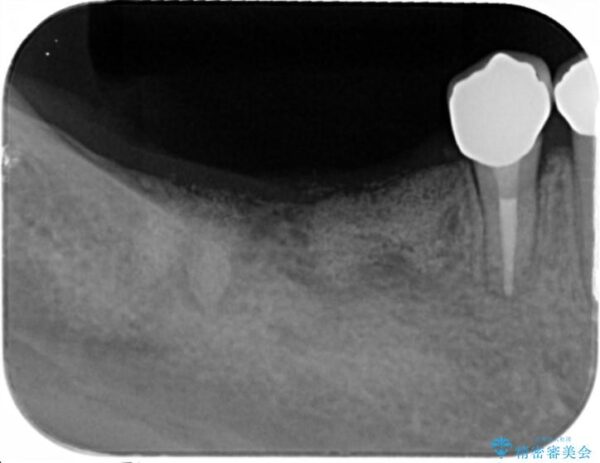

X線写真検査より、クラウンや銀歯の下で歯に大きな虫歯が発生し、抜歯を余儀なくされる状況でした。

虫歯に伴い歯槽骨の吸収も見られたので造骨後、インプラントを用いて咬合機能を回復します。